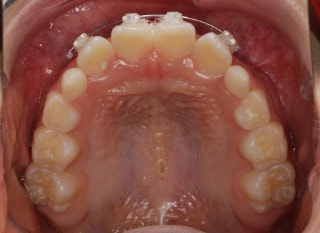

治療前

前歯装置装着時